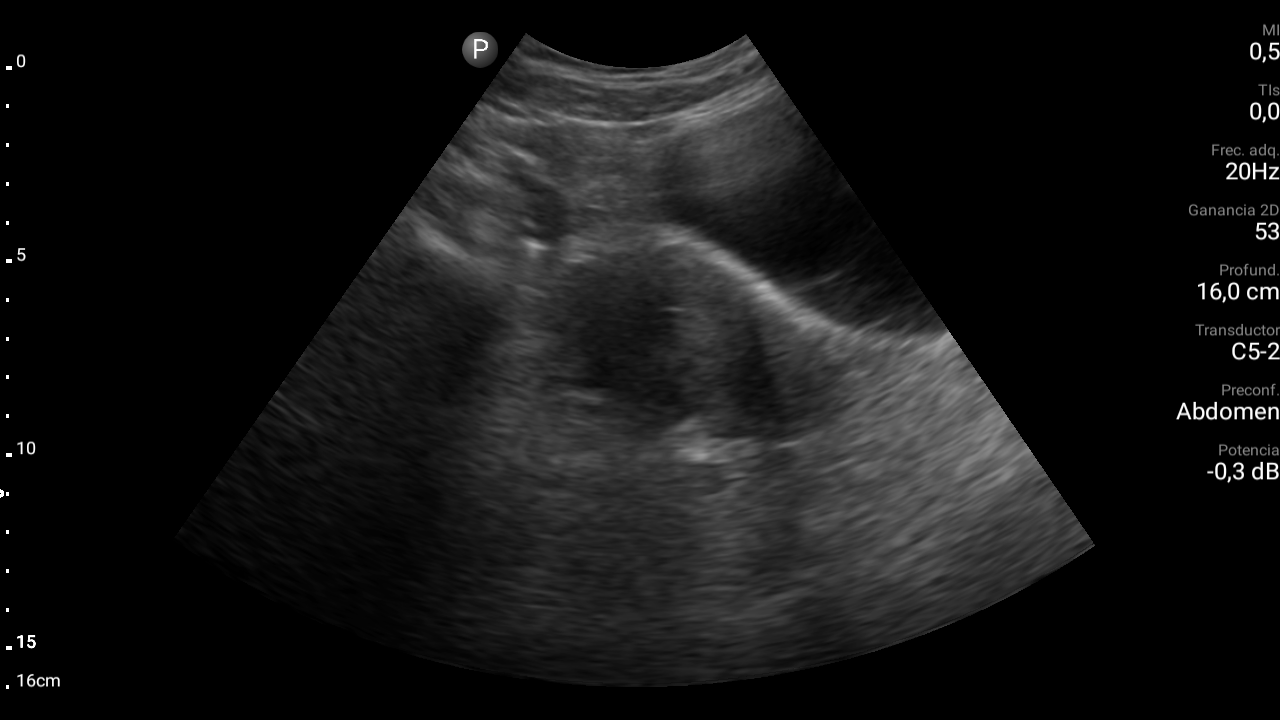

Ecografía abdominal: se observa masa hipoecoica dependiente de útero por lo que se remite de forma preferente a ginecología.

• Ecografía transvaginal: masa uterina compatible con mioma uterino.

Diagnóstico: mioma uterino.